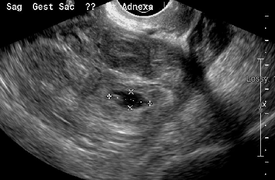

An ultrasound showing a gestational sac with fetal heart in the fallopian tube has a very high specificity of ectopic pregnancy. It involves a long, thin transducer, covered with the conducting gel and a plastic/latex sheath and inserted into the vagina.[32] Transvaginal ultrasonography has a sensitivity of at least 90% for ectopic pregnancy.[5] The diagnostic ultrasonographic finding in ectopic pregnancy is an adnexal mass that moves separately from the ovary. In around 60% of cases, it is an inhomogeneous or a noncystic adnexal mass sometimes known as the "blob sign". It is generally spherical, but a more tubular appearance may be seen in case of hematosalpinx. This sign has been estimated to have a sensitivity of 84% and specificity of 99% in diagnosing ectopic pregnancy.[5] In the study estimating these values, the blob sign had a positive predictive value of 96% and a negative predictive value of 95%.[5] The visualization of an empty extrauterine gestational sac is sometimes known as the "bagel sign", and is present in around 20% of cases.[5] In another 20% of cases, there is visualization of a gestational sac containing a yolk sac or an embryo.[5] Ectopic pregnancies where there is visualization of cardiac activity are sometimes termed "viable ectopic".[5]

Transvaginal ultrasonography of an ectopic pregnancy, showing the field of view in the following image

A "blob sign", which consists of the ectopic pregnancy. The ovary is distinguished from it by having follicles, whereof one is visible in the field. This patient had an intrauterine device (IUD) with progestogen, whose cross-section is visible in the field, leaving an ultrasound shadow distally to it.

Ultrasound image showing an ectopic pregnancy where a gestational sac and fetus has been formed